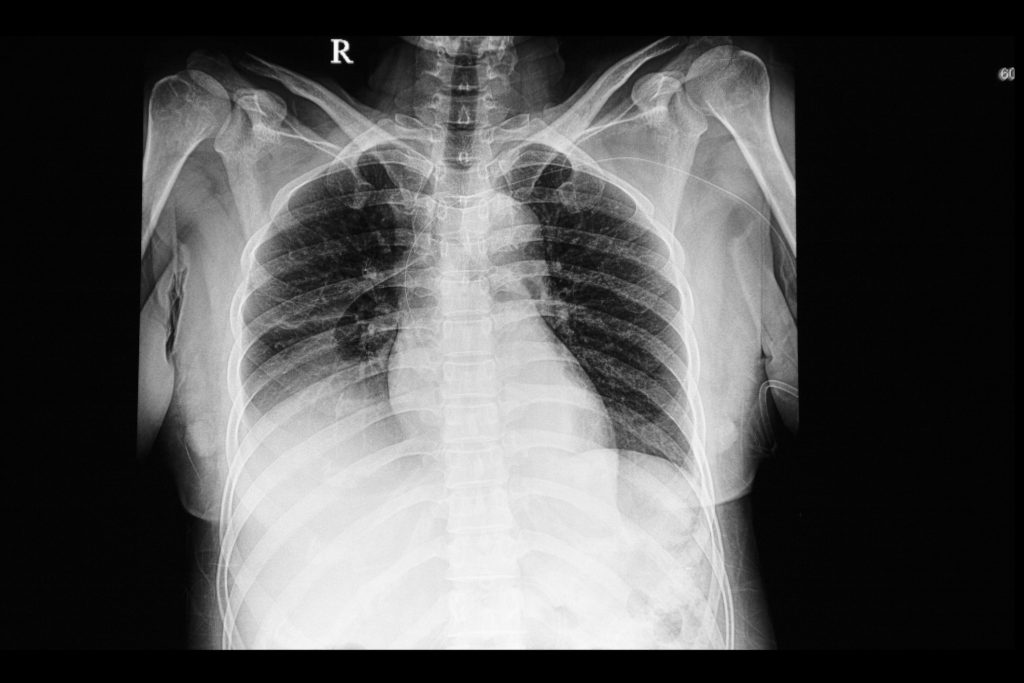

Header image: a chest x-ray film of a patient with right lung pleural effusion. A right heart venous catheter is also shown.